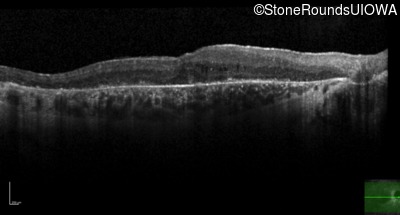

Optical Coherence Tomography - Left - 20/50 -1

Exemplar / OCT Stack

OCT Stack